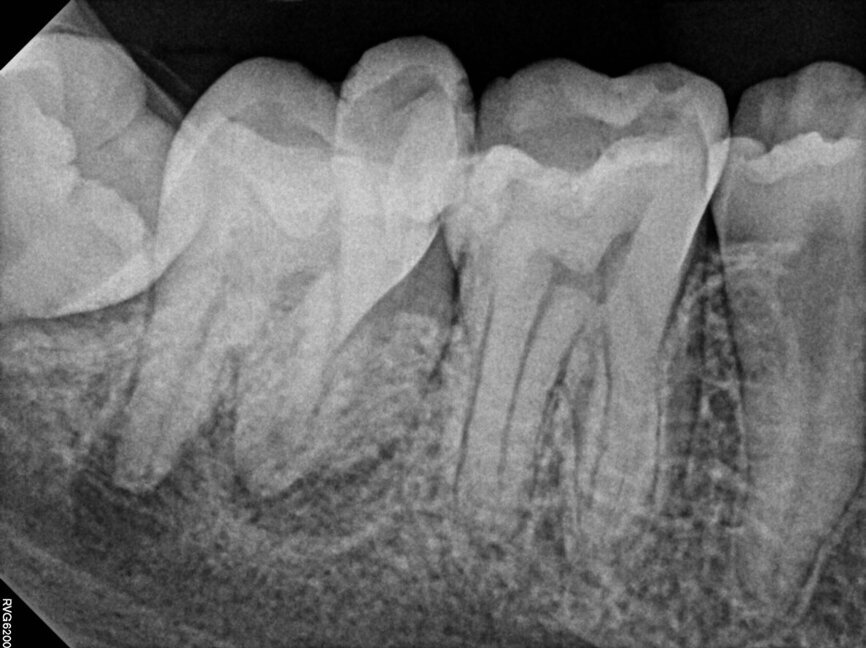

Fig. 17a: Case assisted with CBCT to determine anatomy pre-operatively. Note the multiple cross sections moving apically and the correlation to the 2-D view. Note also the conservative taper in relation to the root width. (Courtesy of Dr. Brett Gilbert)

Fig. 17b: Case assisted with CBCT to determine anatomy pre-operatively. Note the multiple cross sections moving apically and the correlation to the 2-D view. Note also the conservative taper in relation to the root width. (Courtesy of Dr. Brett Gilbert)

Fig. 17c: Case assisted with CBCT to determine anatomy pre-operatively. Note the multiple cross sections moving apically and the correlation to the 2-D view. Note also the conservative taper in relation to the root width. (Courtesy of Dr. Brett Gilbert)

Fig. 17d: Case assisted with CBCT to determine anatomy pre-operatively. Note the multiple cross sections moving apically and the correlation to the 2-D view. Note also the conservative taper in relation to the root width. (Courtesy of Dr. Brett Gilbert)

Fig. 17e: Case assisted with CBCT to determine anatomy pre-operatively. Note the multiple cross sections moving apically and the correlation to the 2-D view. Note also the conservative taper in relation to the root width. (Courtesy of Dr. Brett Gilbert)

Fig. 17f: Case assisted with CBCT to determine anatomy pre-operatively. Note the multiple cross sections moving apically and the correlation to the 2-D view. Note also the conservative taper in relation to the root width. (Courtesy of Dr. Brett Gilbert)

Managing complex anatomy is much simpler if the clinician has a pre-operative road map. The CBCT provides the roadmap and the surgical microscope the lens (literally) through which to visualize the result. Aside from a relaxed patient who is profoundly numb, being able to visualize anatomy by taking a pre-operative (and possibly intra-operative) CBCT and using a surgical microscope during treatment have no substitutes. They are the current “Gold Standard” in that 3-D imaging shows the clinician the true reality of a clinical situation as opposed to the suggestion gained from a 2-D radiograph. Proper interpretation of imaging prior to and/or during endodontic treatment goes a long way in taking the “guesswork” out of identifying canal location and other anatomical complexities as the procedure unfolds. In a 2014 study by El Fayad and Johnson, it was determined that when having a pre-operative CBCT as compared to 2-D radiographs alone, the treatment plan was modified 62 percent of the time. This is a huge game changer to think that the information learned from 3-D imaging changed the plan of treatment over six times out of 10 (Fig. 4).[2]